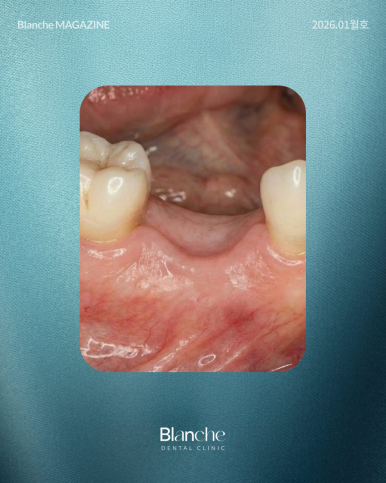

이를 뽑고 방치하면 잇몸뼈는 할 일을 잃고 점점 얇아집니다.

이런 경우에는 임플란트를 심을 '지반' 자체가 부족해지므로

안정적인 결과를 위해 뼈이식이 동반될 가능성이 높습니다.

잇몸 질환이 심해 치아가 흔들려 뽑게 된 경우라면,

주변 뼈가 이미 염증으로 인해 많이 파괴되었을 확률이 큽니다.

이런 상황에서는 임플란트를 심어도 뼈가 나사를 충분히 잡아주지 못하므로,

뼈이식을 통해 무너진 지반을 재건하는 과정이 필수적입니다.